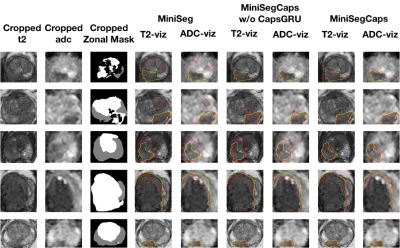

Fig.3 illustrates a visual comparison of the cropped T2, cropped ADC, cropped zonal mask, lesion ground truth, and predicted lesion mask by MiniSegCaps on T2 and ADC images. Our model successfully produced satisfactory segmentation of prostate cancer and revealed the spatial relationship between the zonal mask, lesion on T2, and ADC, which might help lesion location and classification. We also obtained consistent segmentations across adjacent slices within one volume, as shown in Fig.4. Our MiniSegCaps obtained better results than MiniSegCaps w/o CapsGRU, which indicates that CapsGRU captured the spatial information across adjacent slices as expected, boosting the prostate cancer segmentation performance. Moreover, our model achieved acceptable performance on BPH segmentation as shown in Fig.6.

Fig. 3. Visualization of lesion segmentation results among different cases. The yellow contour is the ground truth, and the red contours are from the deep learning predictions.

Fig. 4. Visualization of lesion segmentation results on eight slices from one case. The yellow contour is ground truth, and the red contours are predictions from the MiniSegCaps without or with CapsGRU. MiniSegCaps with CapsGRU can better delineate the prostate cancer contours across different slices in one case compared to that without CapsGRU.